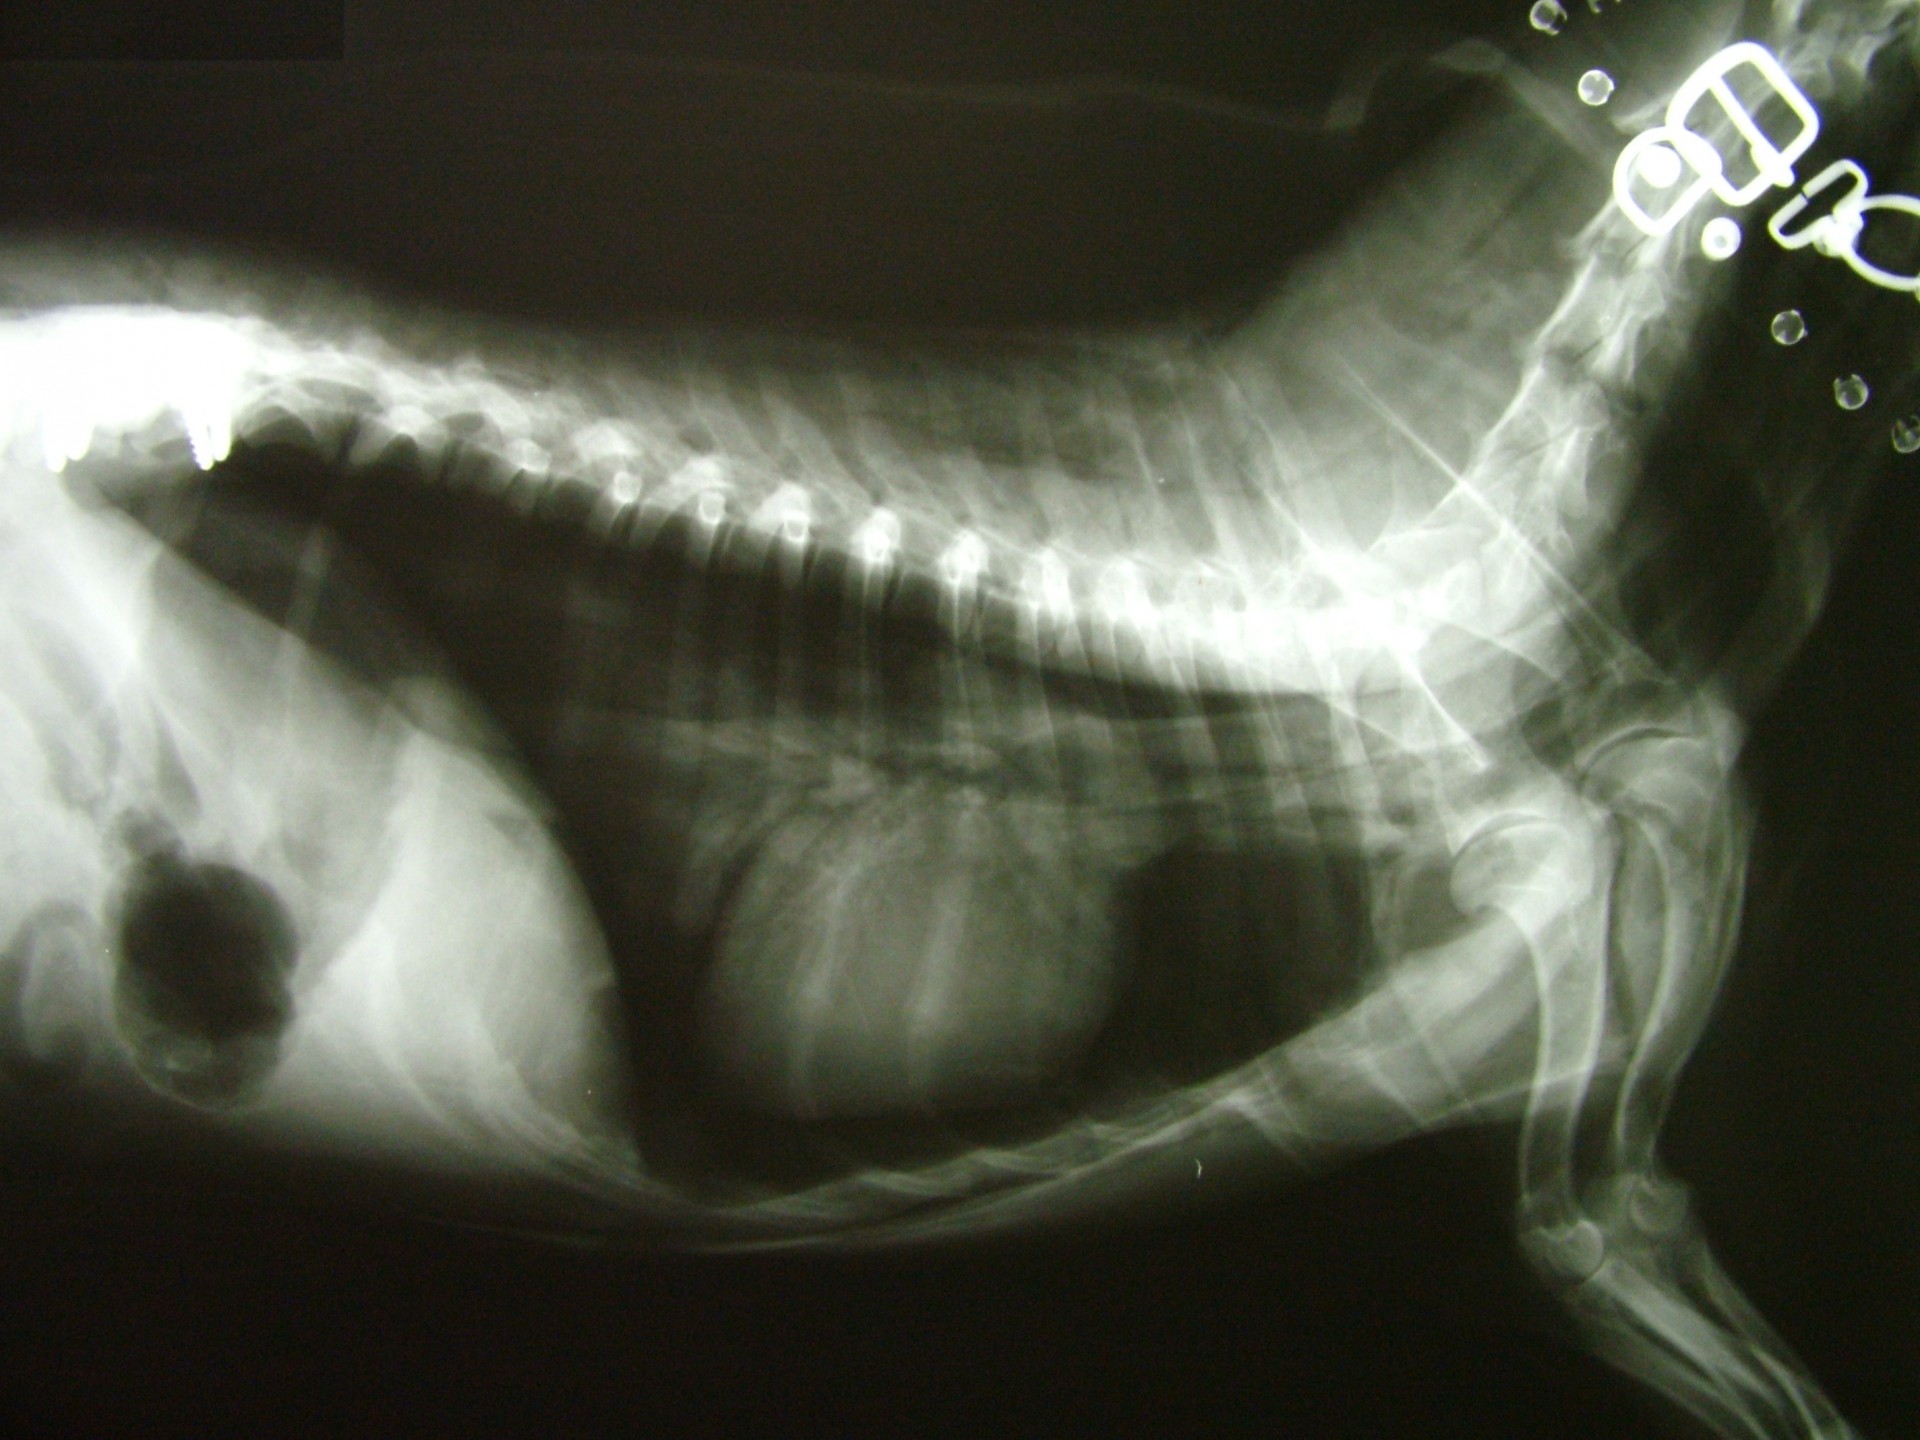

A gerinctörés diagnózisának felállítása komoly döntés elé állítja a tulajdonost és az állatorvost egyaránt. A gerinctörés következtében a gerincvelő minden esetben enyhébb-súlyosabb mértékben sérül. A gerincvelő sérülésének mértékét neurológiai vizsgálattal állapítjuk meg, de a diagnózis felállításához nélkülözhetetlen röntgen felvételről is már információt nyerhetünk a gerincvelő várható állapotáról. A tört végek egymáshoz képest történő kis mértékű elmozdulása esetén a gerincvelő körüli területek bevérzése miatt kialakult neurológiai tünetekkel találkozunk míg nagymértékű elmozdulásuk a gerincvelőt gyakorlatilag olló szerűen elnyírhatja. Így a natív röntgen felvételen a gerinccsatorna elmozdulásából már következtetést vonhatunk le a gerincvelőt ért sérülés mértékéről. A gerincvelő tényleges állapotáról azonban csak neurológiai vizsgálattal győződhetünk meg!

A gerinctörések műtéti ellátása kettős feladatot jelent: egyrészről a törés és elmozdulás következtében kialakult gerincvelő összenyomatást kell megszüntetni, másrészről a tört végeket kell adaptálni és eredeti állapotban - a további elmozdulás megakadályozása érdekében - rögzíteni. A műtéti ellátás során ezért minden esetben az érintett területen a gerinccsatorna felső csontos ívét eltávolítjuk (total laminectomia) így a gerincvelő sérülésének mértéke egyértelműen látható ill. a későbbi összenyomatása elkerülhető.

A törött csigolyatestek adaptációja és rögzítése a nyitott gerinccsatorna mellett komoly kihívást jelent. A későbbi elmozdulás elkerülésére többféle műtéttechnika alkalmazható, melyek közül a csigolyatestek lemezes osteosynthesise ill a fixateur interna használata terjedt el leginkább. Első esetben a sérülés előtti és mögötti csigolyákat lemez és csavarok segítségével egymáshoz rögzítjük, míg az utóbbi esetben a törés előtti és mögötti egy vagy több csigolyatestet két oldalról behelyezett csavarok és egy steril kétkomponensű akrilát műgyanta segítségével rögzítjük.